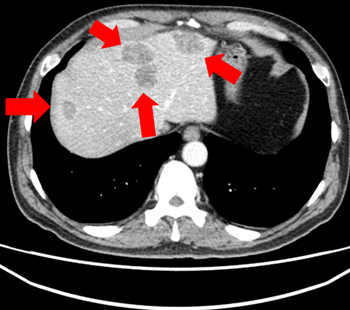

2024.1.30 治疗前

2024.5.21 治疗1个月后

伴随肺转移的肝癌 4期 诊断

10日集中 高频热疗 实施